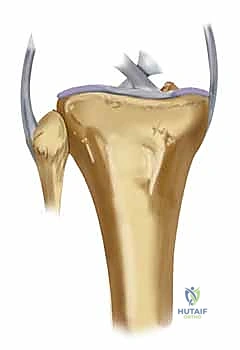

Crucially, the modern orthopedic surgeon must possess a heightened awareness of the posteromedial shear fragment. Historically underappreciated, this specific fracture morphology occurs when the knee is subjected to an axial load while in a flexed and varus position. The medial femoral condyle shears off the posteromedial aspect of the tibial plateau. This is not merely a radiologic curiosity; it represents a highly unstable fracture-dislocation variant. The posteromedial fragment often encompasses the insertion of the posterior cruciate ligament (PCL) and the meniscotibial ligaments. Failure to recognize and independently stabilize this fragment with dedicated posterior or posteromedial buttress plating will inevitably lead to catastrophic posterior subluxation of the femur and rapid varus collapse of the mechanical axis, regardless of the robustness of the lateral fixation.

While the Schatzker system is invaluable, the AO/OTA classification provides a more granular, alphanumeric categorization that is essential for academic research and precise surgical auditing. Bicondylar fractures fall under the 41-C category (complete articular fractures). These are further subdivided into C1 (articular simple, metaphyseal simple), C2 (articular simple, metaphyseal multifragmentary), and C3 (articular multifragmentary). The C3 variant, representing the most complex morphology with extreme articular comminution, tests the limits of surgical reconstruction. Furthermore, modern CT-based classifications, such as the Luo three-column concept, have revolutionized our understanding by dividing the plateau into medial, lateral, and posterior columns. This three-dimensional conceptualization is critical, as it mandates that each fractured column must be independently addressed and stabilized to prevent multi-planar collapse.

The proximal tibia is an asymmetric osseous expansion designed to receive and dissipate the massive loads transmitted across the knee joint. The medial tibial plateau is the primary load-bearing surface. It is anatomically larger, concave in both the sagittal and coronal planes, and supported by bone that is significantly denser and stronger than its lateral counterpart. During the normal gait cycle, the medial plateau sustains approximately 60% to 75% of the total compressive force. This inherent concavity and dense subchondral architecture make it relatively resistant to pure depression fractures; instead, it typically fails in a shear-split pattern.

Conversely, the lateral tibial plateau is smaller, sits slightly higher anatomically, and is distinctly convex in the sagittal plane. The subchondral bone here is notably thinner and more porous. Consequently, the lateral plateau is highly susceptible to depression and impaction injuries when struck by the convex lateral femoral condyle. Understanding these morphological differences is critical during surgical reconstruction. Elevation of the lateral plateau often leaves a massive cavitary void that mandates structural bone grafting to prevent post-operative subsidence, whereas the medial plateau often requires robust anti-glide plating to resist shear forces.